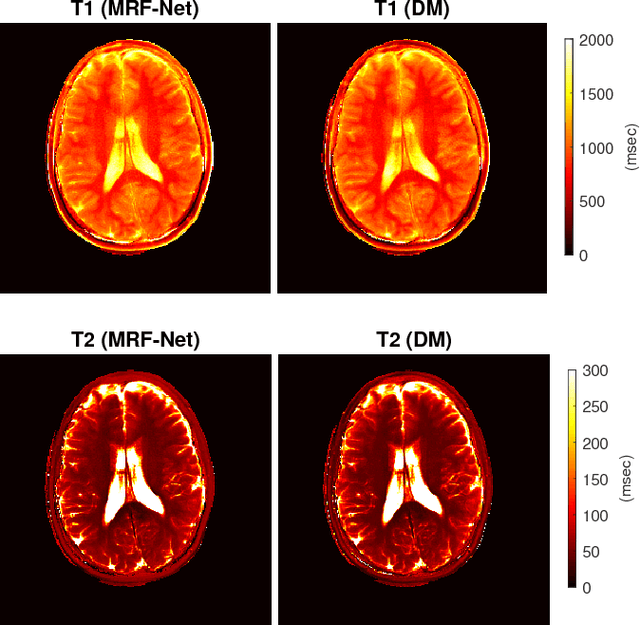

Abstract:Current popular methods for Magnetic Resonance Fingerprint (MRF) recovery are bottlenecked by the heavy storage and computation requirements of a dictionary-matching (DM) step due to the growing size and complexity of the fingerprint dictionaries in multi-parametric quantitative MRI applications. In this paper we study a deep learning approach to address these shortcomings. Coupled with a dimensionality reduction first layer, the proposed MRF-Net is able to reconstruct quantitative maps by saving more than 60 times in memory and computations required for a DM baseline. Fine-grid manifold enumeration i.e. the MRF dictionary is only used for training the network and not during image reconstruction. We show that the MRF-Net provides a piece-wise affine approximation to the Bloch response manifold projection and that rather than memorizing the dictionary, the network efficiently clusters this manifold and learns a set of hierarchical matched-filters for affine regression of the NMR characteristics in each segment.

Abstract:The main purpose of this study is to show that a highly accelerated Cartesian MRF scheme using a multi-shot EPI readout (i.e. multi-shot EPI-MRF) can produce good quality multi-parametric maps such as T1, T2 and proton density (PD) in a sufficiently short scan duration that is similar to conventional MRF. This multi-shot approach allows considerable subsampling while traversing the entire k-space trajectory, can yield better SNR, reduced blurring, less distortion and can also be used to collect higher resolution data compared to existing single-shot EPI-MRF implementations. The generated parametric maps are compared to an accelerated spiral MRF implementation with the same acquisition parameters to evaluate the performance of this method. Additionally, an iterative reconstruction algorithm is applied to improve the accuracy of parametric map estimations and the fast convergence of EPI-MRF is also demonstrated.